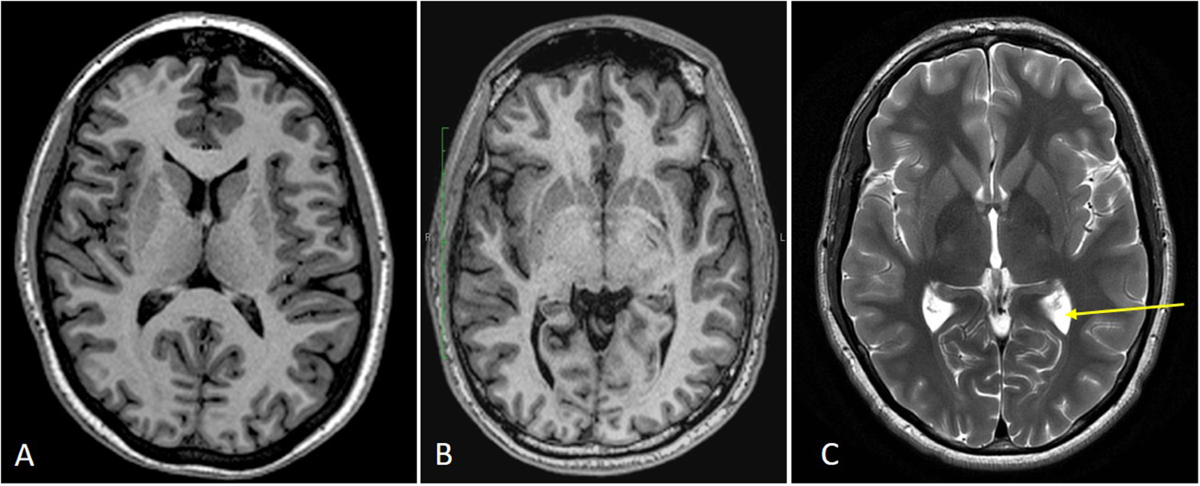

Lesiones que la resonancia puede detectar en TCE leve

Lesión axonal difusa (microlesiones microscópicas)

La aceleración y desaceleración brusca puede generar daño en las conexiones neuronales (axones).

Estas lesiones pueden ser invisibles en TC pero detectables en RM mediante:

- Secuencias FLAIR

- Difusión (DWI)

- Tensor de difusión (DTI)

Son responsables de síntomas cognitivos persistentes.

Microhemorragias cerebrales

Pequeñas hemorragias puntiformes pueden pasar desapercibidas en tomografía.

La resonancia, especialmente con secuencias de susceptibilidad magnética (SWI), puede identificarlas con alta sensibilidad.

Contusiones corticales pequeñas

Pequeñas áreas de edema o contusión pueden no ser evidentes inicialmente en TC.

La resonancia permite visualizar:

- Edema cerebral focal

- Inflamación cortical

- Evolución de la lesión en el tiempo